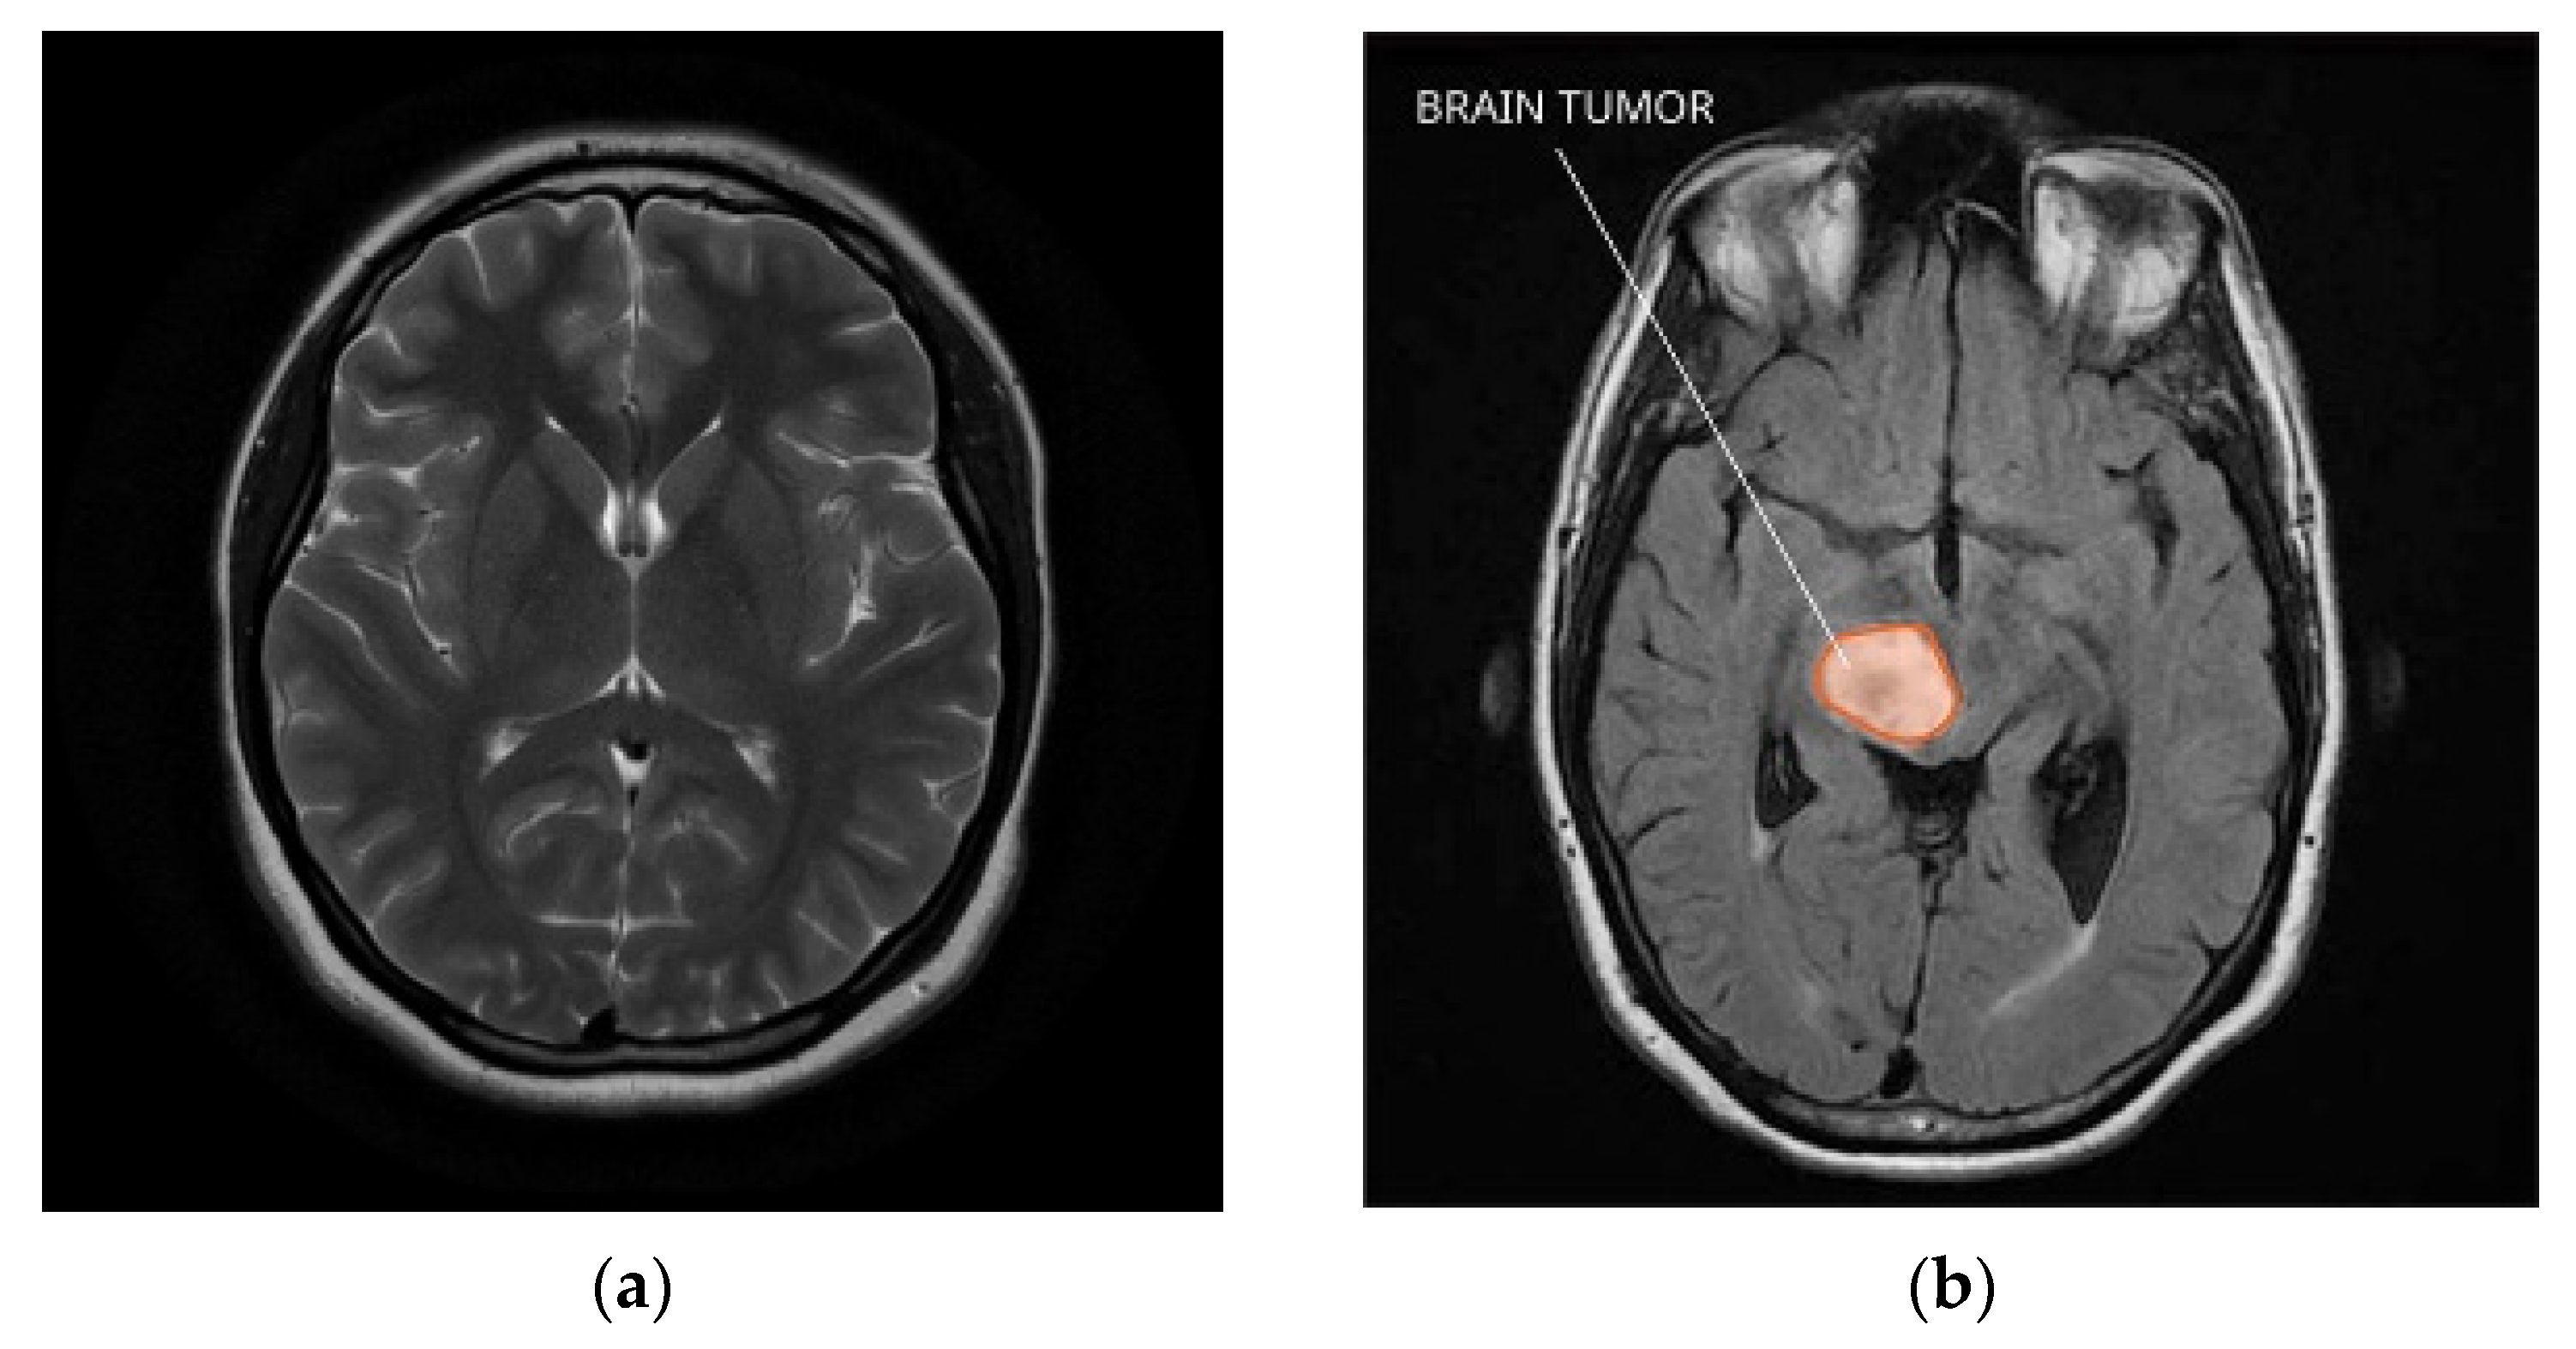

- Image Processing: There are many imaging techniques that use the brain, including Magnetic Resonance Imaging (MRI), Computed Tomography (CT), and Positron Emission Tomography (PET). Each model has its own strengths and limitations, and the choice of model will depend on the specific issue and capability. MRI is the most widely used for brain imaging. It has a high resolution and similar texture, making it ideal for determining the location and size of a tumor. MRI can also provide information about the blood supply to the tumor and the presence of enemas (swelling). MRI is noninvasive and contains no ionizing radiation, making it safe and versatile. However, MRI can be expensive and time-consuming, and patients may feel claustrophobic or uncomfortable during the scan. CT is another method that can be used to image brain tumors. It uses X-rays to create detailed images of the brain that can be used to determine the location and size of tumors. CT is faster, cheaper, and sometimes more effective than MRI. However, CT contains ionizing radiation, which can be dangerous to patients, and provides less contrast between soft tissues than MRI. PET is a technique that can be used to identify areas of the brain with increased metabolic activity that may indicate the presence of cancer. PET scans are often used with CT or MRI scans to give more details regarding the tumor’s dimensions and position. PET scans involve injections of antibodies that can be harmful to patients and are more expensive and more common than MRI or CT. For in-depth investigations, MRI is often preferred because of its high resolution and tissue homogeneity. MRI images can be used to create 3D volumes of the brain. They can be applied to deep learning model instructional design and evaluation. CT and PET images can also be used for in-depth investigations but may require additional pre-processing steps to improve image quality and reduce noise. In general, the choice of modality depends on the specific questions and available resources, but MRI is generally considered the gold standard for neuroimaging.